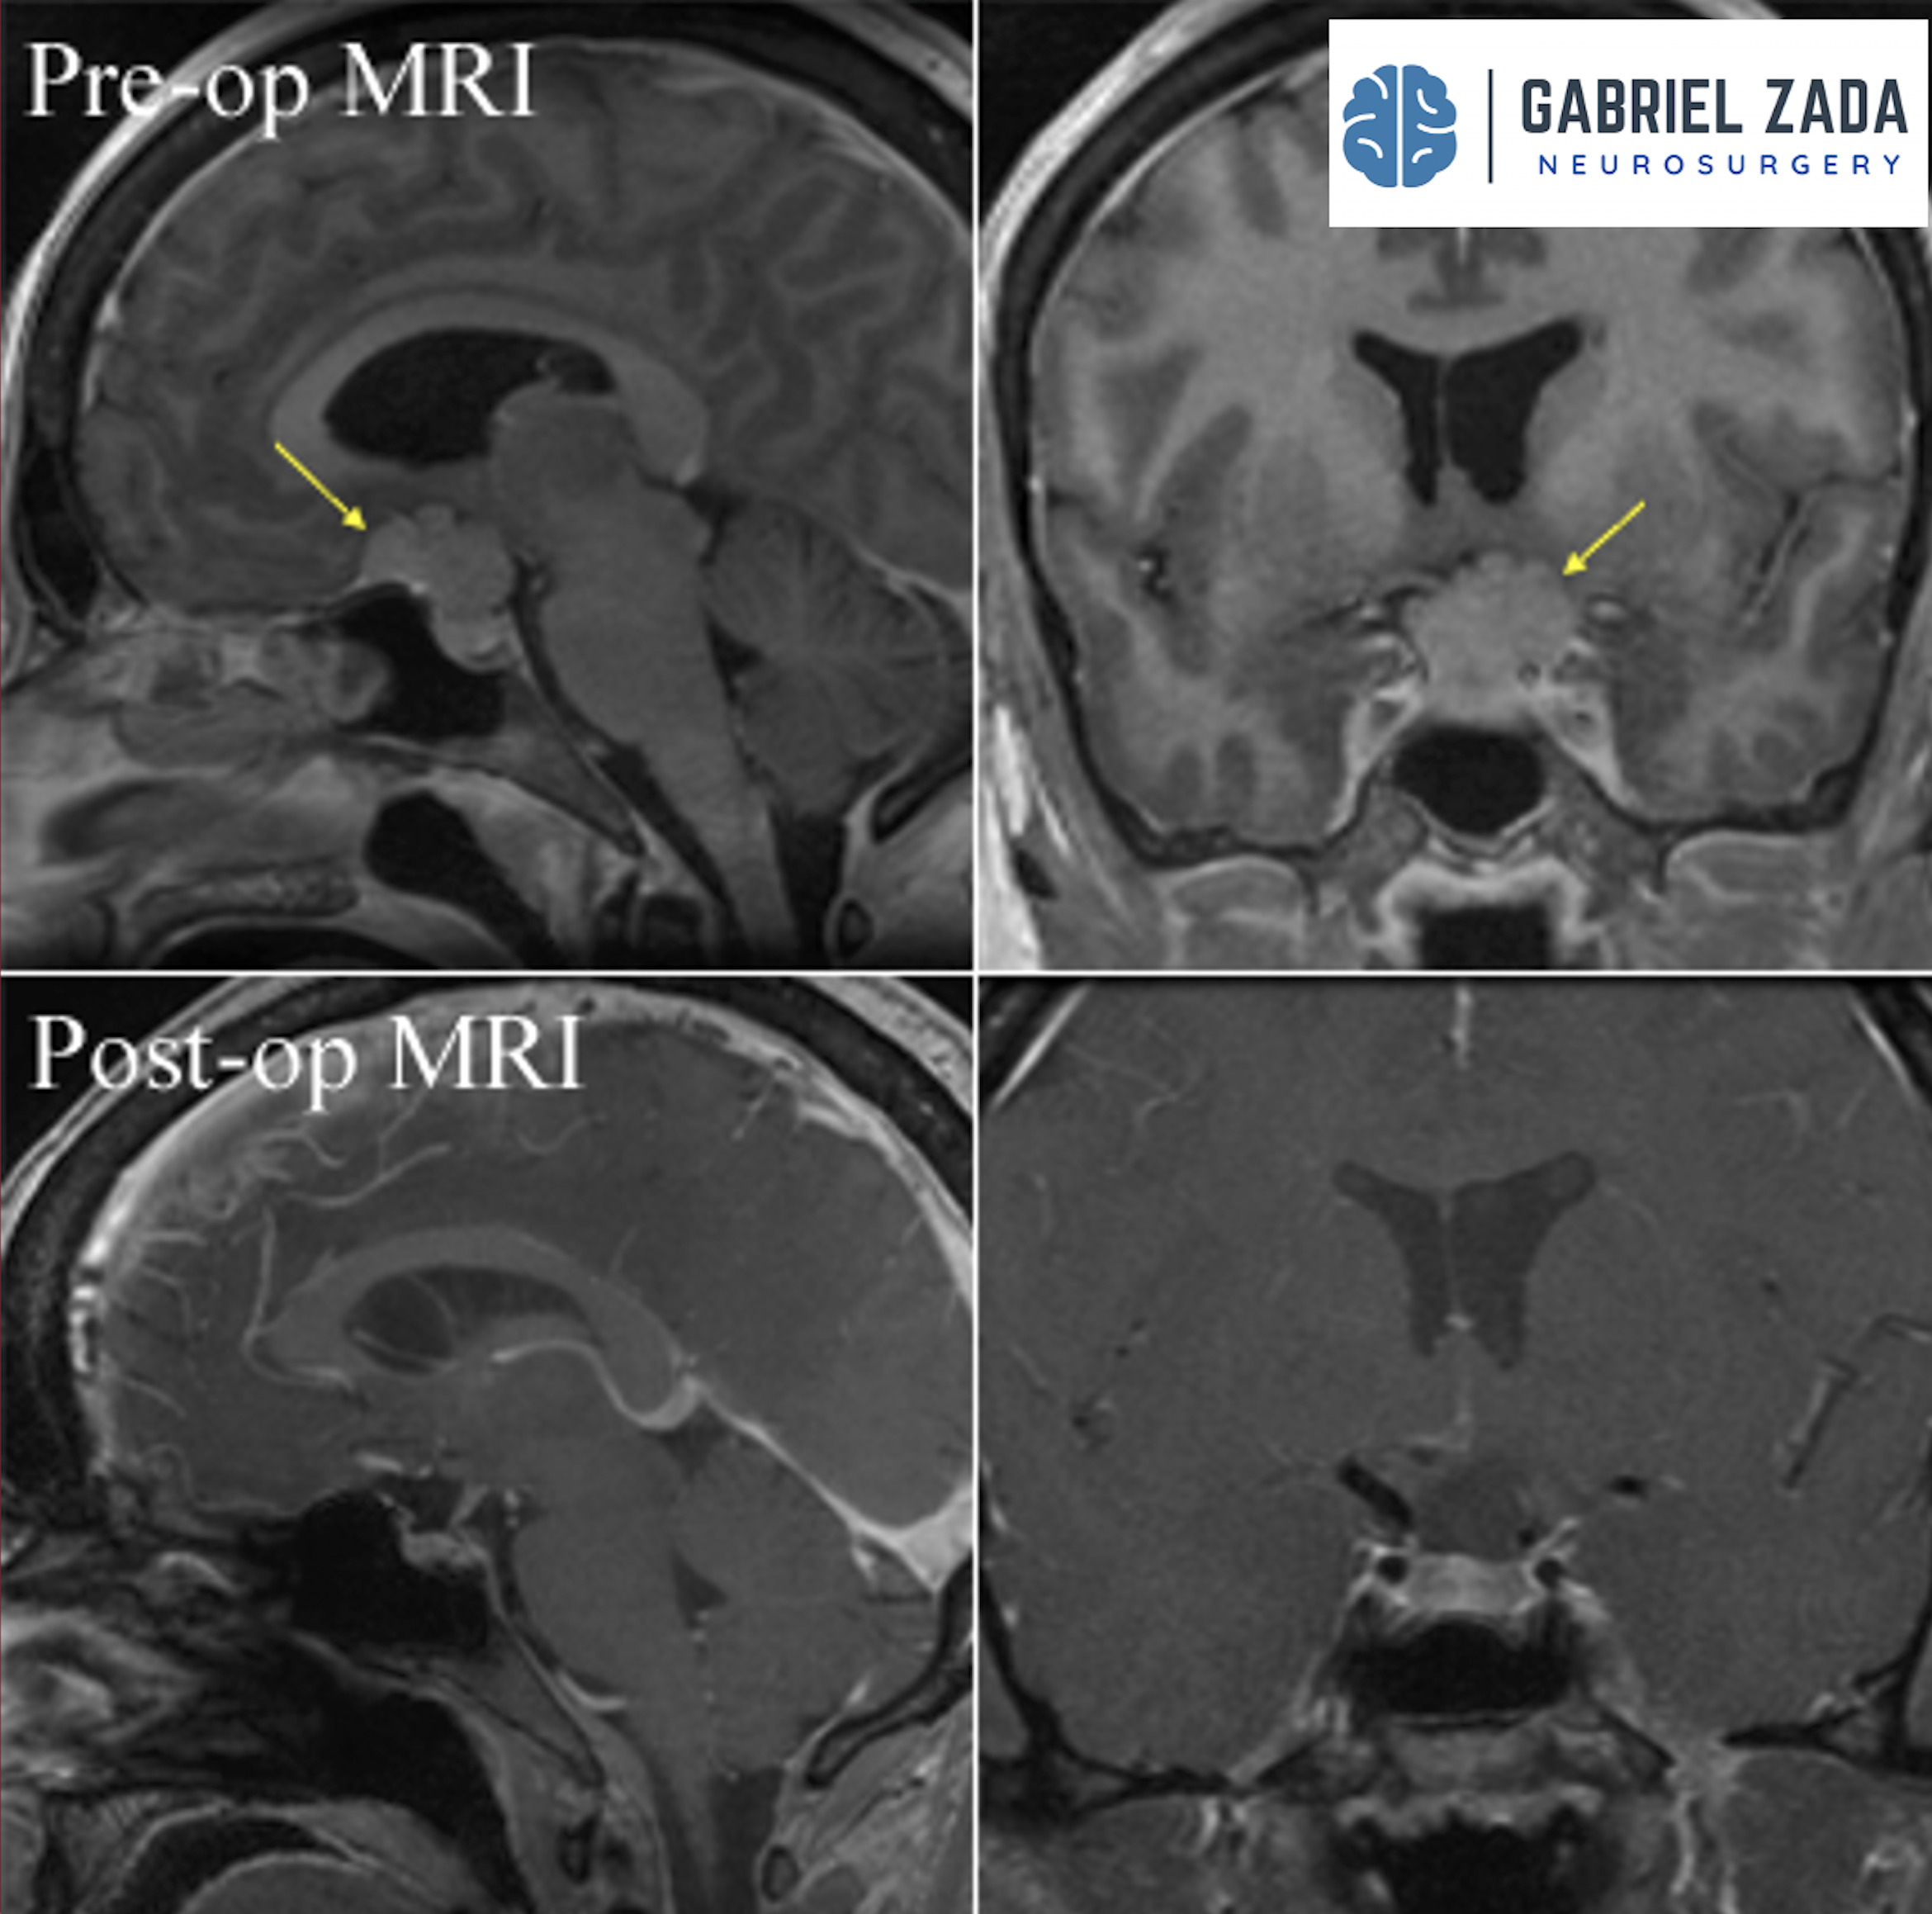

Explore this comprehensive gallery featuring pre‑ and post‑operative imaging of patients with skull‑base tumors treated by Gabriel Zada, MD, MS, FAANS, FACS. These cases highlight Dr. Zada’s expertise in advanced neurosurgical techniques and outcomes.

*Representative cases shown for educational purposes. All images de-identified. Individual results vary.